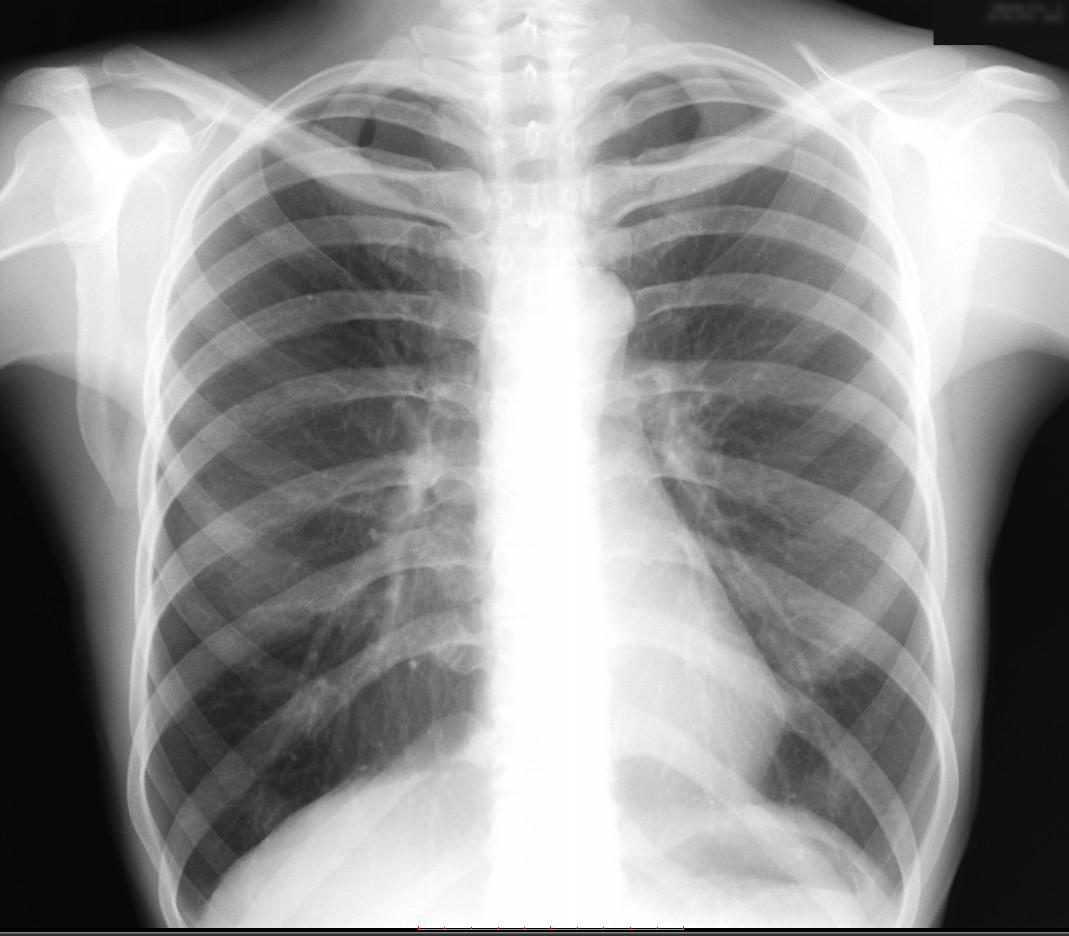

Рентген здоровых легких: примеры снимков и советы